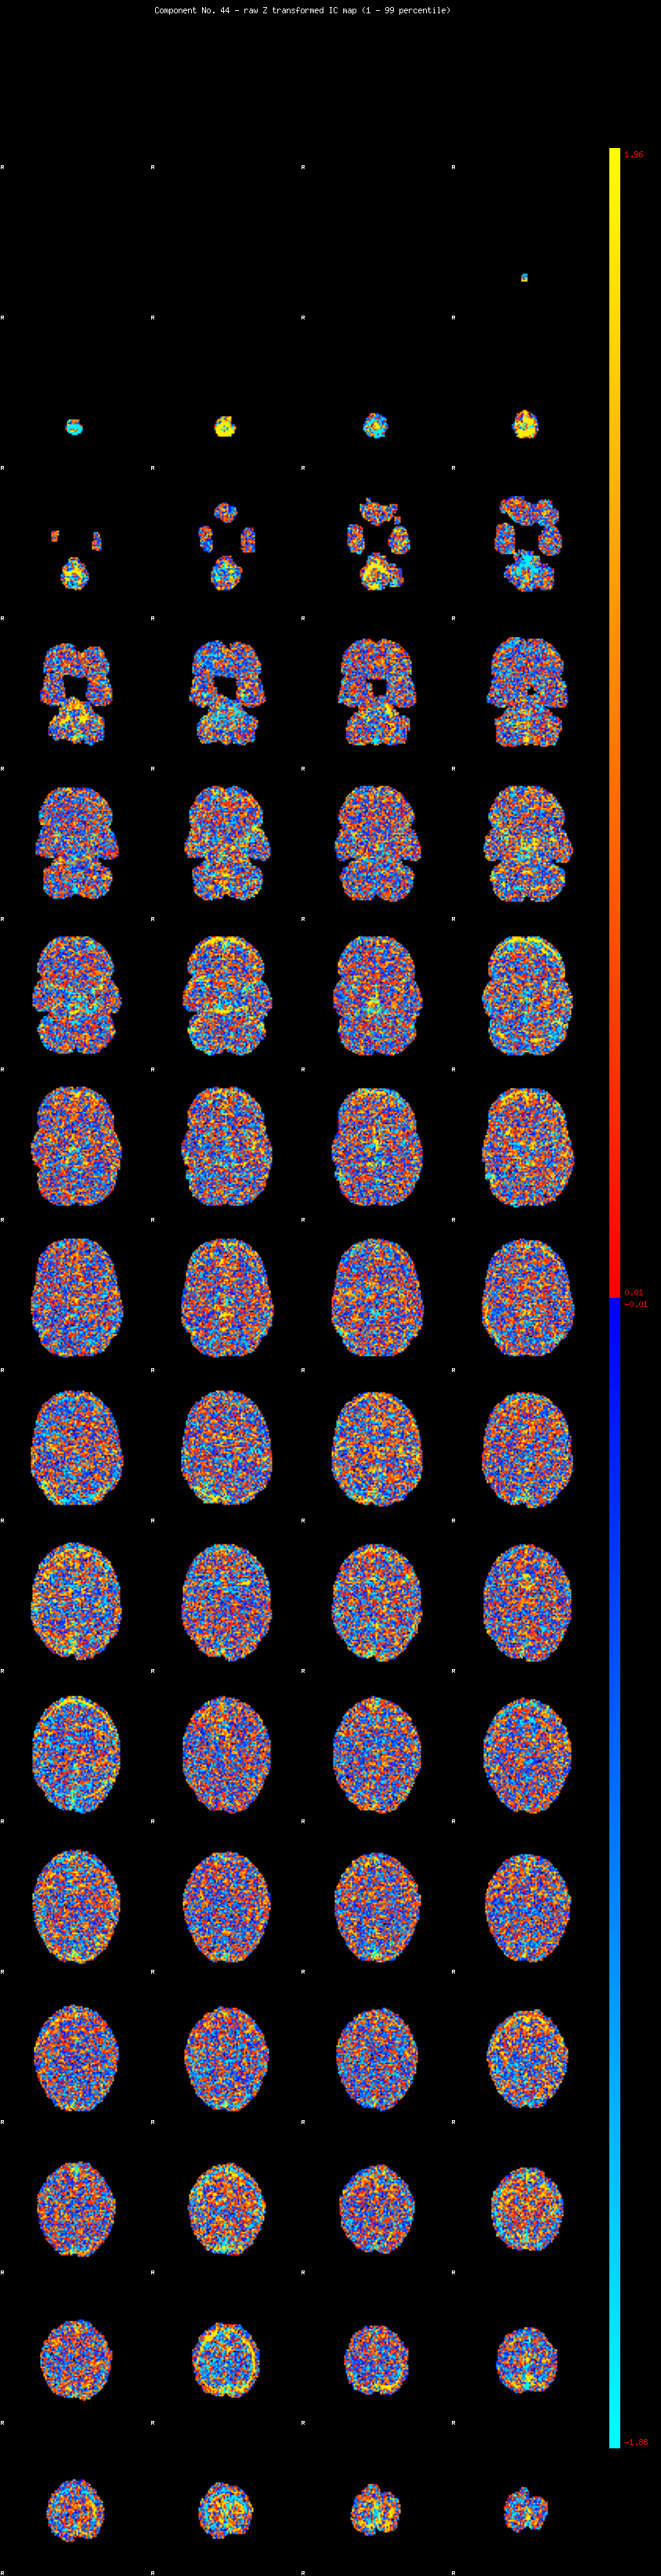

IC_44 Mixture Model fit

Means : -0.000000 2.610789 -2.456160

Vars : 1.000000 2.485155 2.000530

Prop. : 0.950842 0.027361 0.021797